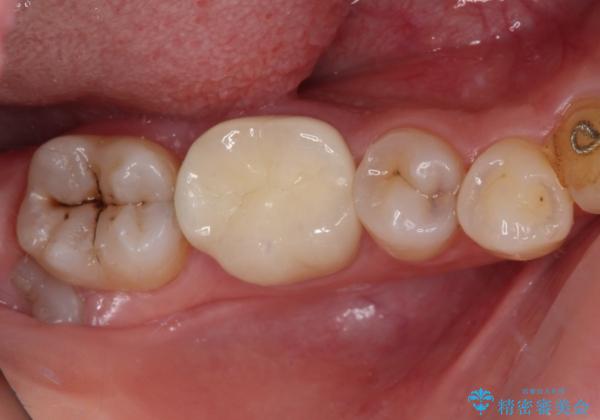

速やかにラバーダム下にて根管治療を行うこととし、その後オールセラミッククラウンにて補綴治療を行うこととしました。

治療期間中、痛みが生じることはなく、処置後3か月経過しましたが良好な状態を保っています。